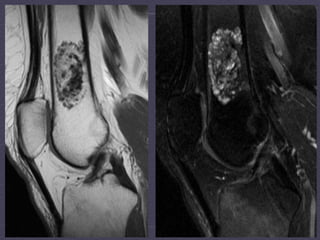

T1-­‐weighted,   T2-­‐weighted,   T1   fat-­‐satura:on   post-­‐contrast   MRI   studies  demonstrates  a  septated  mass  with  low  T1  signal,  increased   T2  signal,  and  rim  enhancement  within  the  intertrochanteric  region   of  the  right  femur